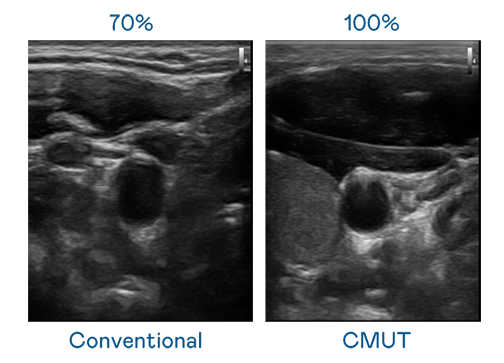

CMUT 技术是一种用电容式微机电元件来产生超音波讯号的技术。与传统 PZT 压电式技术相比,CMUT 频宽增加 30%,更宽频的超音波讯号让影像解析度大幅提升,是实现高影像品质医疗超音波扫描、促进精准医疗发展的关键技术。

大频宽带来超清晰影像

超音波影像的解析度高低,首先取决于探头能发出的讯号频宽。新航 CMUT 可提供高清晰的超音波讯号,提供高频宽、高灵敏度、影像纹理细节更高的超音波影像,协助医护人员缩短影像判读时间及利用精准的医疗影像进行诊断。